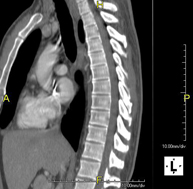

- Thoracic spine CT

Radiological test that involves capturing high-definition anatomical images of the thoracic vertebrae using a CT (computed tomography) scanner. Indicated for: acute/chronic back pain, trauma, spinal misalignment.